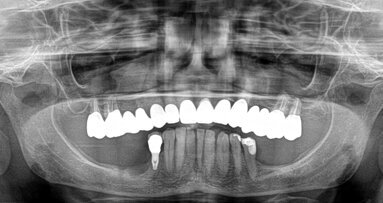

La tomografia panoramica dentale mostra la situazione 18 mesi dopo l’impianto.